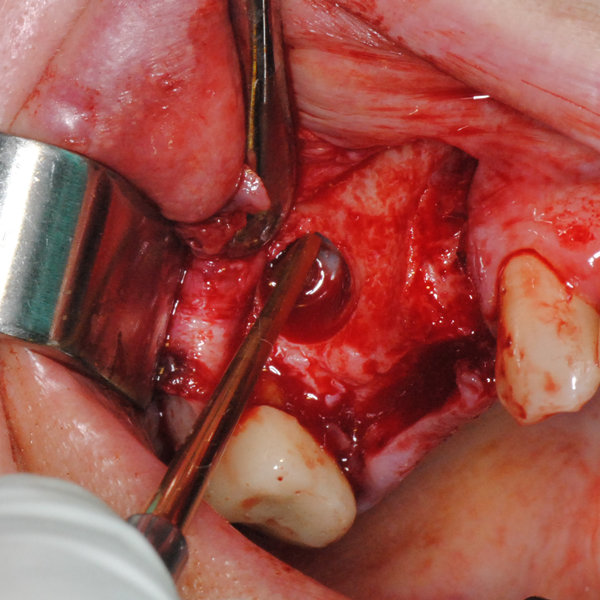

Отворен максиларен синус в началото на интервенцията. Случаят е интересен със следното - твърде атипична форма на трепанационния отвор. На какво се дължи на това - на лошо планиране на оперативния достъп или на нещо друго? Дължи се на факта, че отначало въпросната намеса беше планирана като балонен синуслифт; за съжаление обаче мембраната на синуса се разкъса и надуването на балона стана невъзможно.